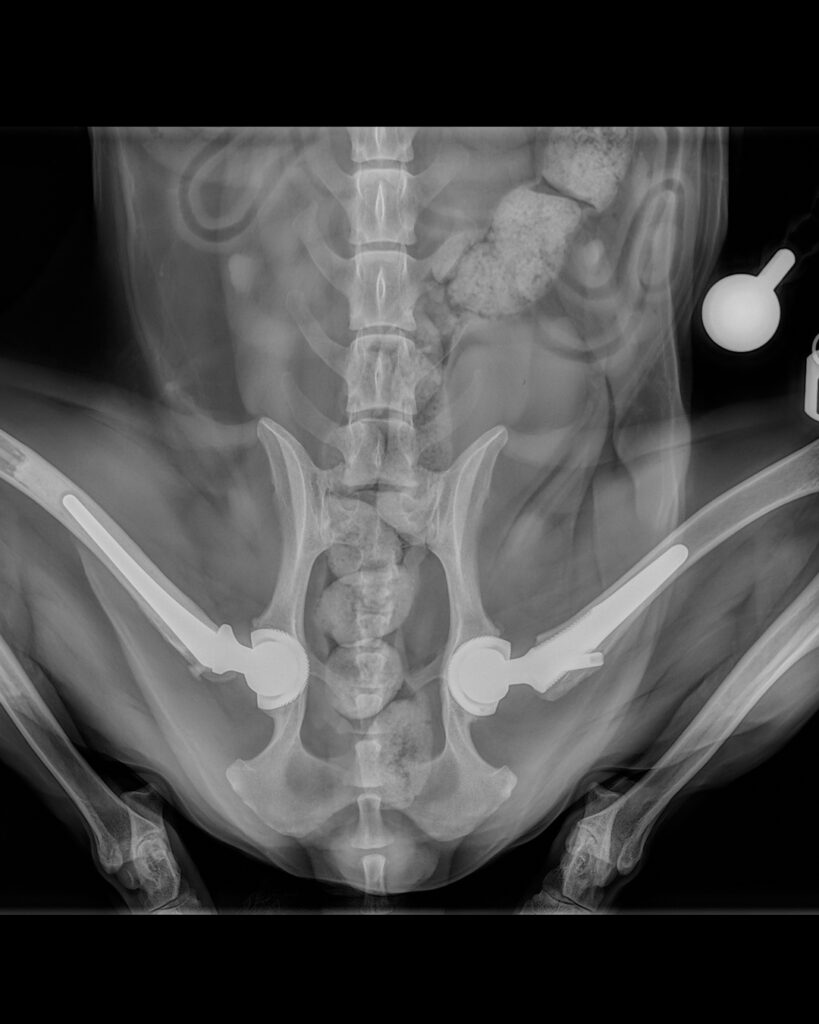

Rosey’s X-rays for her hip dysplasia

Super spaniel Rosey came in with her mum, Senior Surgical Technician Kirsty, with some ongoing lameness and stiffness on her hind limbs.

As a first step, her orthopaedic surgeon requested for some radiographs to be taken using one of our three X-ray units to better understand what was happening in Rosey’s bones and joints. X-ray images are really effective at showing bony detail and providing an overall assessment of the bone integrity and alignment.

They showed that poor Rosey was suffering from bilateral hip dysplasia and associated osteoarthritis, but fortunately, total hip replacements were a treatment option and Kirsty opted to go ahead with the procedure for her canine friend, replacing the right hip first and the left nine months later.

Postoperative radiographs were also taken immediately following surgery and at regular intervals after each operation to demonstrate good implant placement and bone healing.

Rosey made a swift recovery and is now zooming around on her new hips, enjoying life pain-free.